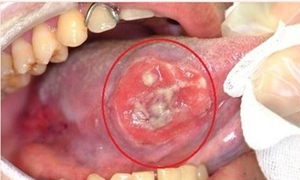

舌疮,中医病名。是指舌体、舌边、舌尖等处发生白色溃烂的小疮、红赤疼痛、伴见发热,因痛不能饮食、流口水、烦躁不安,是一种常见的舌头疾病。舌疮常反复发作,经久难以愈合。本病可发于任何年龄,发病率女多于男。多由外感热病、心火上炎、胃火熏蒸等所致。本病常见于复发性舌疮。

1、多发生在舌体,以舌尖,舌边多见。

2、单发、多发性圆形或椭圆形浅表小溃疡,局部红肿疼痛。

4、常反复发作,愈合后不留疤痕。